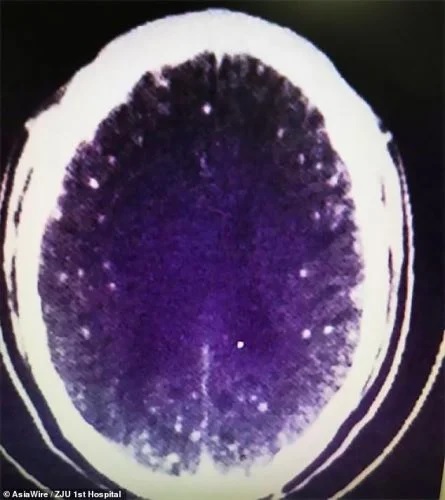

In spite of just a month passing since he consumed the half-cooked pork, specialists immediately recognized the reason for Zhongfa’s seizures and swooning episodes. His body was totally contaminated with tapeworms. These unwanted visitors had made themselves at home in his mind, lungs, and different pieces of his body. The worm hatchlings had spread all through his body by means of his circulation system.

The hatchlings entered Zhongfa’s body through his stomach related framework and went through his circulation system to his cerebrum and lungs. These child worms wriggled into his body tissue and shaped pimples. On the off chance that these pimples rot, they can cause diseases. Individuals with this equivalent issue as Zhongfa frequently report cerebral pains, seizures, visual deficiency, and dementia. Notwithstanding, these side effects don’t necessarily in every case show up right away. Once in a while it can require a long time for the worm hatchlings to arrive at the cerebrum and lungs.

When these hatchlings structure pimples close to the mind or sensory system, it can bring about a perilous contamination called cysticercosis. On account of Zhongfa, the hatchlings had caused various space-possessing sores in his cerebrum, as well as pimples in his lungs and chest muscles.

Dr. Huang Jianrong from the Partnered Clinic of Zhenjiang College Institute of Medication was worried about Zhongfa’s condition. That is the reason he requested mind and chest X-rays for the patient.

“He had various sores in his cerebrum, yet he likewise had blisters in his lungs and chest muscles,” Dr. Huang said. “Various patients answer contrastingly to the contamination, contingent upon where the parasites are. For this situation, he encountered seizures and blacked out, however others with sores in their lungs could encounter a ton of hacking.”